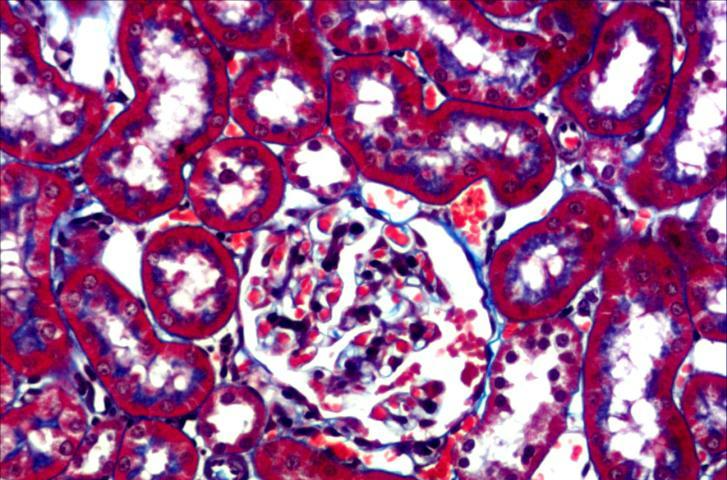

Masson染色(MT染色)是結(jié)締組織染色中最經(jīng)典的一種方法,又稱馬松染色,是顯示組織中纖維的主要方法之一,是膠原纖維染色權(quán)威而經(jīng)典的技術(shù)方法。

該法染色原理與陰離子染料分子的大小和組織的滲透有關(guān),分子的大小由分子量來體現(xiàn),小分子量易穿透結(jié)構(gòu)致密、滲透性低的組織;而大分子量則只能進(jìn)入結(jié)構(gòu)疏松的、滲透性高的組織。

然而,淡綠或苯胺藍(lán)的分子量都很大,因此Masson染色后肌纖維呈紅色,膠原纖維呈綠色或藍(lán)色,主要用于區(qū)分膠原纖維和肌纖維。

使用小鼠肝臟標(biāo)本進(jìn)行MT染色時

使用deColorizing Solution 1和2進(jìn)行脫色

左至右:MT染色→脫色→HE染色

(數(shù)據(jù)提供:麻布大學(xué)小澤秋沙先生、坂上元榮先生)